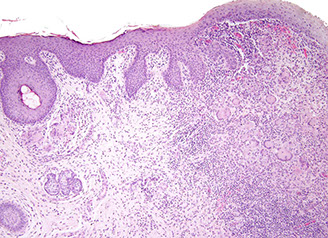

Inflammatory Cloacogenic Polyp

Has both squamous and columnar epithelium, as arises from anterior portion of transitional zone presenting c prolapse which can cause hematochezia

Micro: tubulovillous c ulceration, crypts penetrate to submucosa, lots of fibromuscular straoma into mucosa

Inflammatory Cloacogenic Polyps